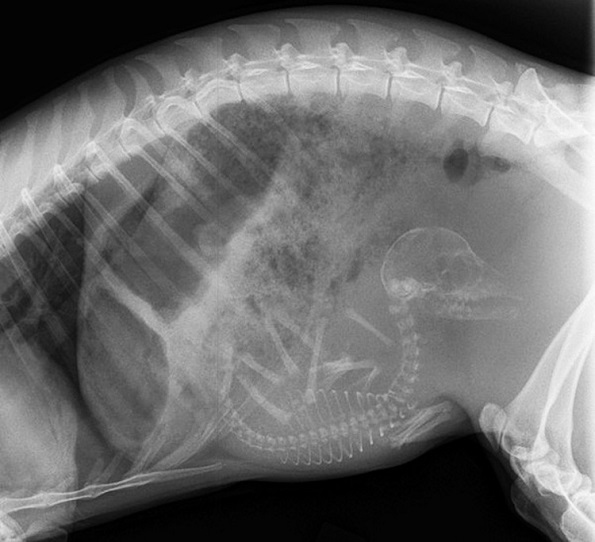

3. Бремена мачка

Мачките може да забременат од околу 4-месечна возраст, доколку не бидат стерилизирани. На околу 45 дена од бременоста, скелетите на малите мачиња ќе бидат доволно оформени за да се појават на рендгенските снимки.